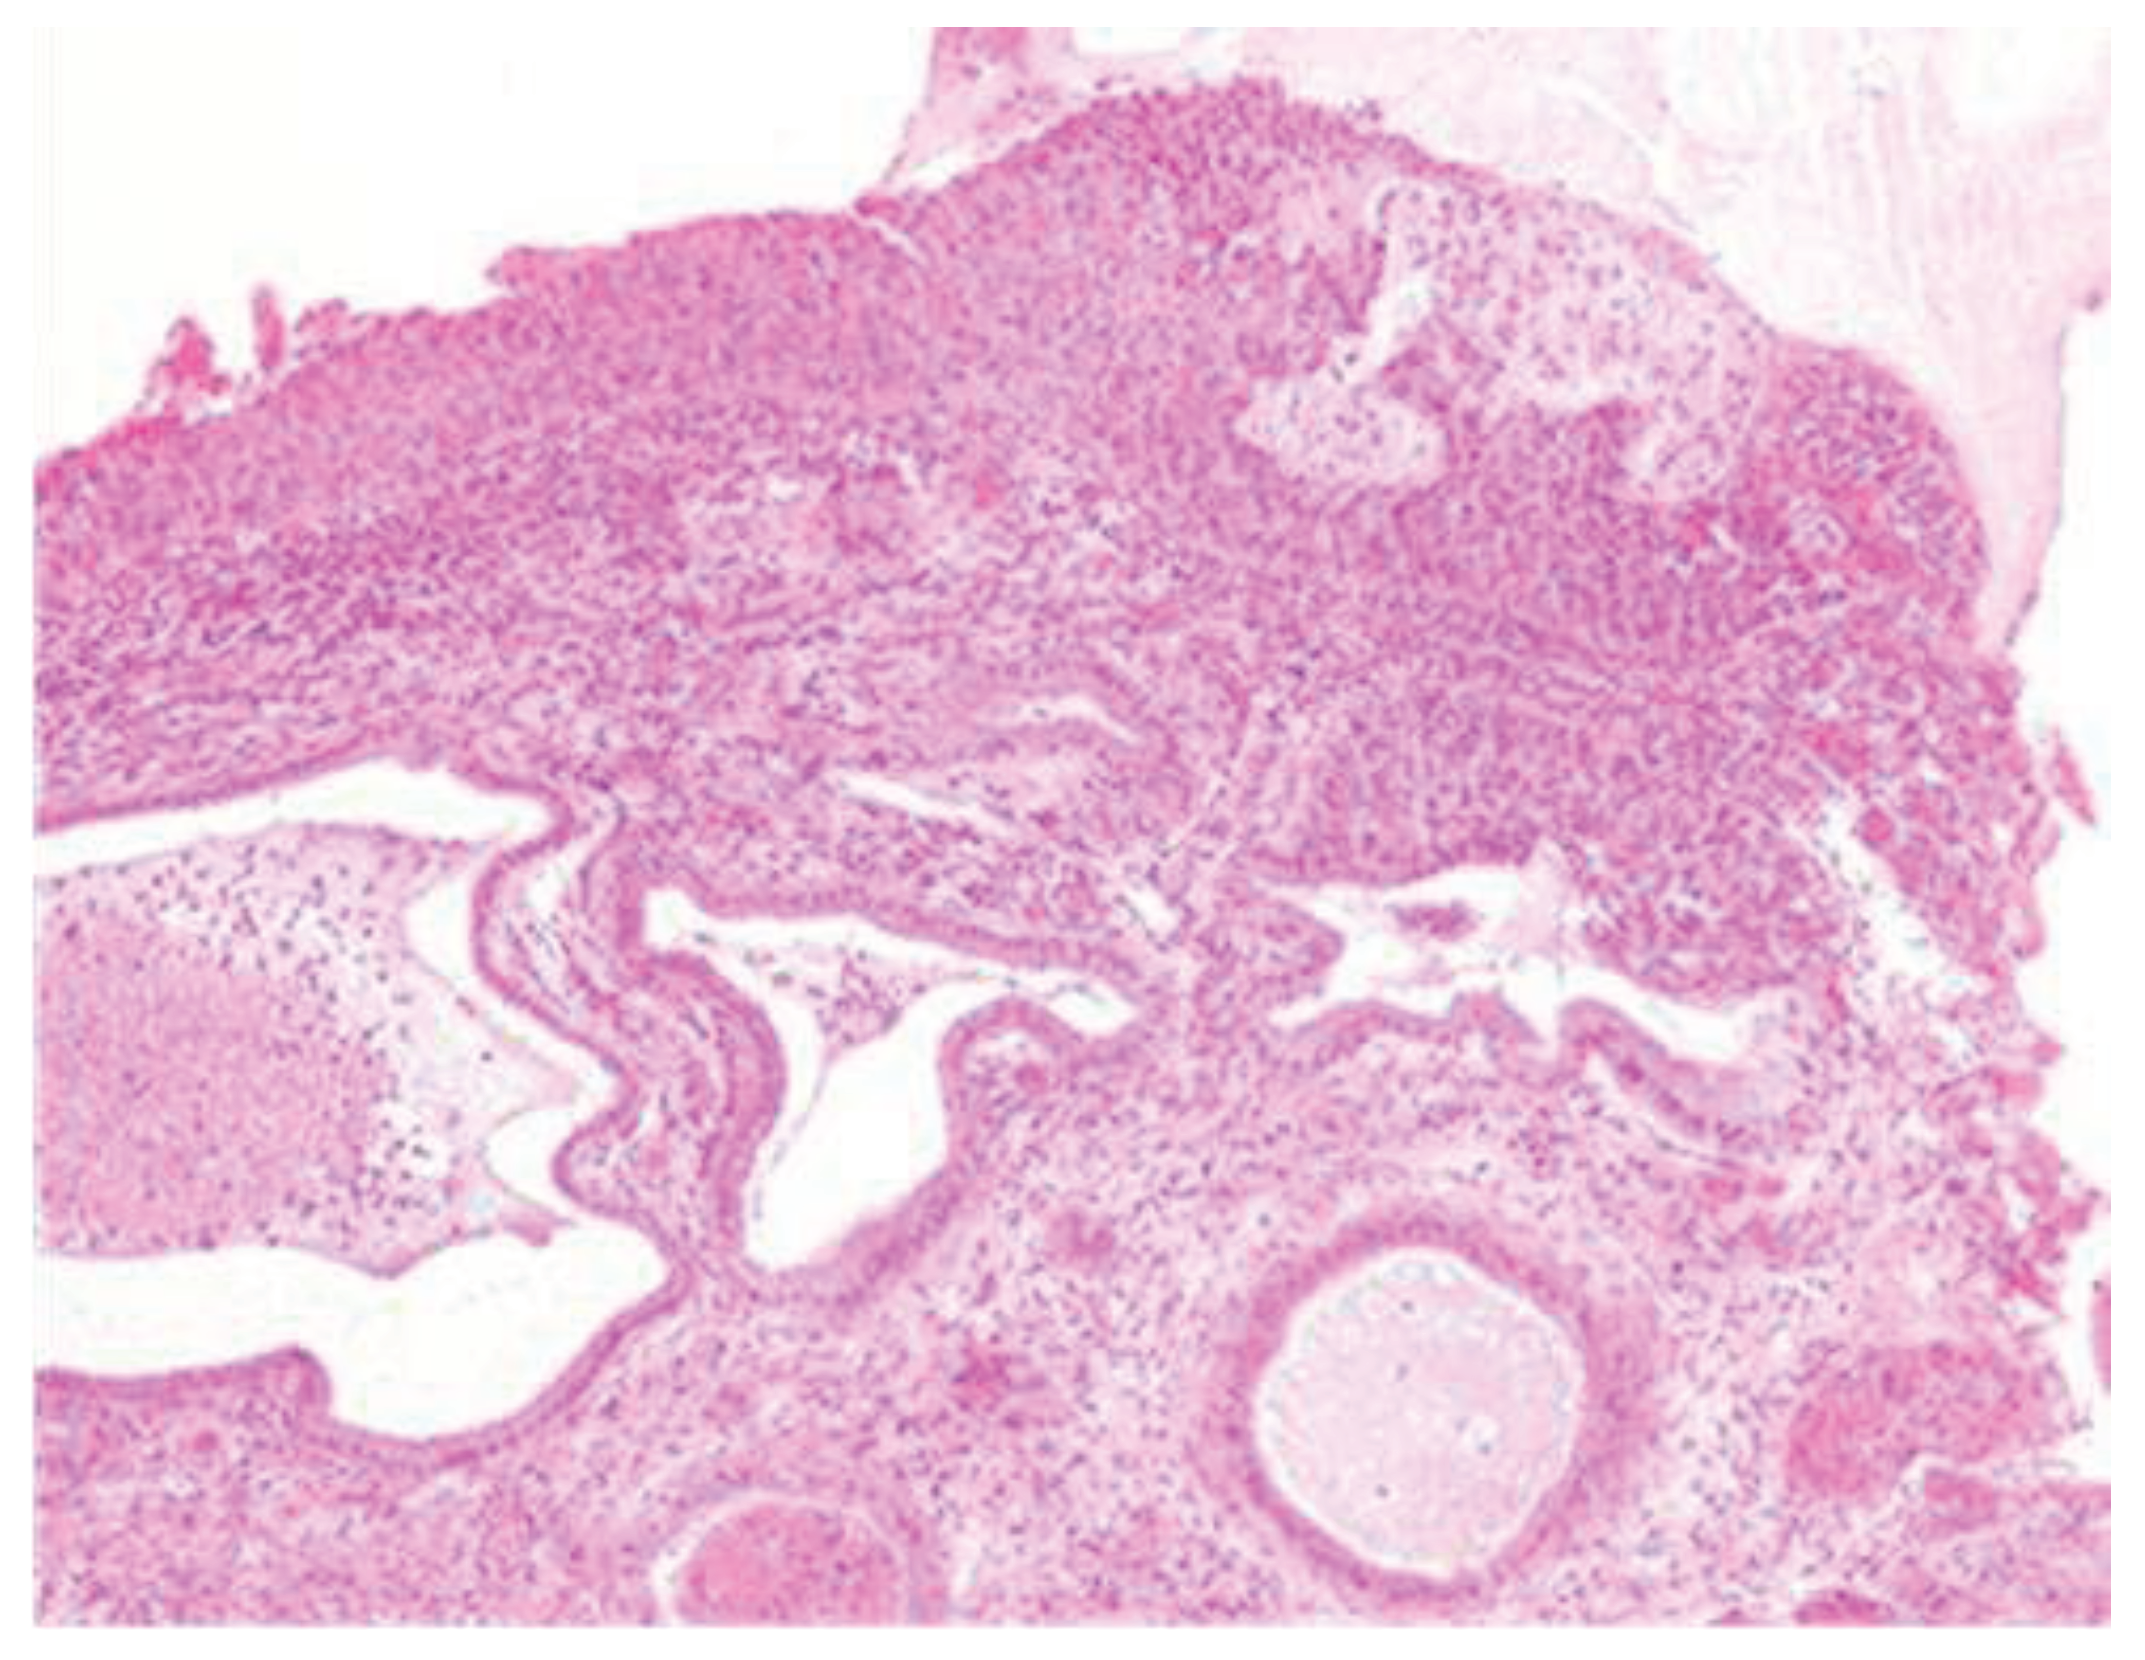

Morphologically, enlarged and hyperchromatic nuclei, clumped chromatin, irregularities, and notches in the nuclear membrane, and altered nuclear/cytoplasmic ratio can be observed. Mitotic figures at various levels are also frequent (Figure 3 and Figure 4).

Figure 3-4. CIN3 histological sample.

The lesion was completely removed; in the small cone performed on the remaining cervical canal, therefore on the portion of the cervix that was not removed, no histological lesion is present (Figure 5).